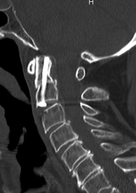

Insgesamt sind Erkrankungen und Verletzungen im Bereich der Halswirbelsäule zahlenmäßig seltener als im Bereich der Brust- und Lendenwirbelsäule. Da die Halswirbelsäule aber eine freie Verbindungsstruktur zwischen Kopf und Rumpf darstellt und das Rückenmark beinhaltet, können Erkrankungen und Verletzungen erheblich spezifische Auswirkungen nach sich ziehen. Zudem kann sie aufgrund enger Kontakte zu verschiedenen Organsystemen hierduch beeinflusst werden, was häufig ein interdisziplinäres Vorgehen erfordert.

Meistens können Schmerzsyndrome der Halswirbelsäule rein konservativ oder in fortgeschritteneren Fällen interventionell-schmerztherapeutisch behandelt werden. Dennoch gibt es viele Erkrankungen oder Verletzungen, die ein operatives Vorgehen erforderlich machen. Dies kann neben Schmerzen insbesondere bei bestehenden oder drohenden Instabilitäten oder Rückenmarks- bzw. Nervenschädigungen der Fall sein.

Um die Halswirbelsäule in allen Fällen optimal und bedarfsgerecht versorgen zu können, müssen neben den konservativen und interventionellen Maßnahmen alle operativen Zugänge von vorne und hinten jeweils vom Kopf bis zur Brustwirbelsäule durchgeführt werden können. Zudem muss die Infrastruktur Tag und Nacht auf Maximalversorgung und interdisziplinäres Vorgehen ausgerichtet sein.

Am Zentrum für Wirbelsäulenchirurgie und Schmerztherapie werden sämtliche Erkrankungen und Verletzungen der Halswirbelsäule und der angrenzenden Strukturen konservativ, interventionell oder mit allen zur Verfügung stehenden Operationstechniken in großer Anzahl behandelt, so dass auf diesem Gebiet große Erfahrungen vorliegen. Wenn notwendig stehen Maximalversorgung und interdisziplinäres Vorgehen 24 Stunden am Tag zur Vergügung.

Schmerzsyndrome der Halswirbelsäule; Bandscheibenvorfall; Verschleiß der Bandscheiben; Spinalkanalstenose (Verengung des Wirbelkanals); Instabilitäten; Spondylolisthesis (Wirbelgleiten), Myelopathie (Schädigung des Rückenmarkes); Querschnittslähmung; Erkrankungen bei Kinder und Heranwachsenden (z. B. Formveränderungen, Skoliosen, Kyphosen, angeborene Wachstumsstörungen, Verletzungen, Entzündungen, Tumore und Metastasen); Verletzungen des Rückenmarks; Wirbelkörperbrüche; Deformitäten (Formveränderungen, Skoliose, Kyphose); Tumore und Metastasen; Infektionen; Spondylodiszitis (Infektion von Bandscheiben und Wirbelkörper); rheumatische Instabilitäten der Halswirbelsäule sowie zwischen Kopf und Halswirbelsäule; Verengungen des Foramen magnum; muskulärer Schiefhals; Syndrome durch die erste Rippe; etc.

alle konservativen Maßnahmen; interventionelle Schmerztherapie aller Bereiche; vollendoskopische und mikrochirurgische Bandscheibenoperationen; Bandscheibenprothese; Stabilisierungen und Versteifungsoperationen von vorne und hinten; Stabilisierungen und Erweiterungen des Kopf-Halsüberganges; Erweiterungen des Foramen magnum; Rekonstruktion von Fehlbildungen und Formveränderungen; Erweiterungen des Wirbelkanals; Entfernung von Wirbelkörpern mit Wirbelkörperersatz; Entfernung von Tumoren und Metastasen; Operation von Infektionen; Operationen bei Kindern und Heranwachsenden; Operationen an der ersten Rippe; Operation des muskulären Schiefhalses; etc.